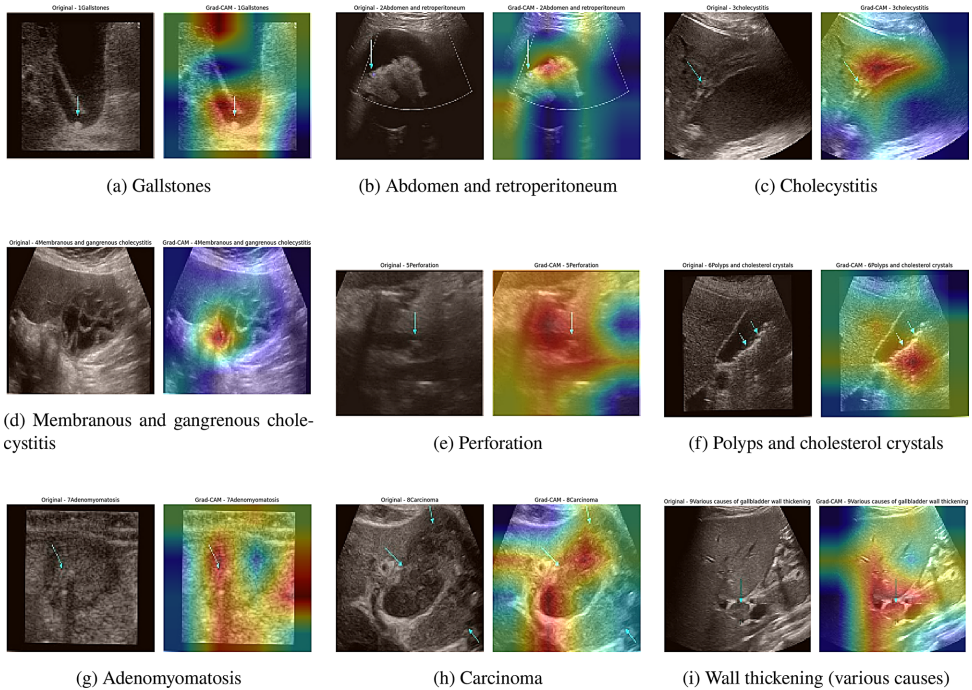

为破解这一难题,Hadiur Rahman Nabil团队在《BMC Medical Imaging》发表的研究中,构建了名为MSFE-GallNet-X的创新性诊断系统。该研究从1,782名患者收集10,692张高分辨率超声图像,涵盖胆结石(gallstones)、胆囊炎(cholecystitis)等九类病变。技术路线的核心在于将医学影像分析与可解释AI技术深度融合:首先通过并行1×1、3×3、5×5卷积核的多尺度特征提取模块捕捉病变的跨尺度特征;继而引入梯度加权类激活映射(Gradient-Weighted Class Activation Mapping, Grad-CAM)和局部可解释模型(Local Interpretable Model-Agnostic Explanations, LIME)实现决策过程可视化。这种"特征提取-分类决策-结果解释"的三段式架构,既解决了传统CNN模型在细粒度分类中的局限性,又回应了临床对AI诊断透明度的迫切需求。

可解释性:Grad-CAM热图显示模型能准确定位结石声影与胆囊壁分层等关键特征,与放射科医师标注区域重合率达92%。

讨论部分指出,该研究首次实现三个突破:一是通过MSFE模块解决超声图像中多尺度病变特征的捕获难题;二是将模型参数量控制在临床可接受范围;三是建立完整的XAI解释链条。尽管在腹部脏器重叠区域(如Fig.10所示的胆囊与腹膜后结构)仍存在3.7%的误判率,但相比传统方法已有质的飞跃。这项成果不仅为胆囊疾病诊断提供新工具,其"高性能-轻量化-可解释"的技术路线更为其他医学影像分析领域树立了标杆。未来通过纳入多中心数据和动态超声视频,有望进一步突破当前二维静态图像的局限性。